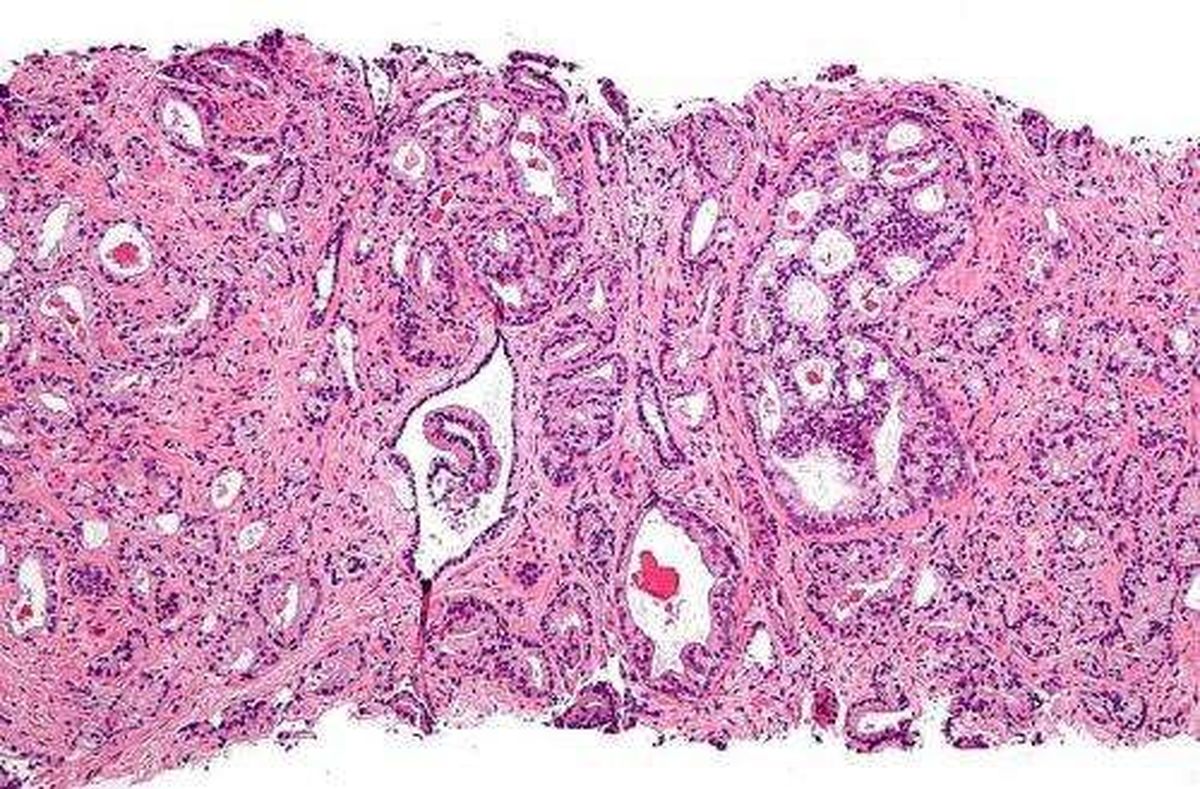

تشخیص سرطان پروستات با سرعت و بدون نمونه برداری

محققان دانشکده پزشکی جان هاپکینز در آمریکا موفق به توسعه یک آزمایش ساده ادرار شده‌اند که بدون نمونه برداری و روش‌های غیر تهاجمی، سرطان پروستات را با سرعت و دقت بالا تشخیص می‌دهد.